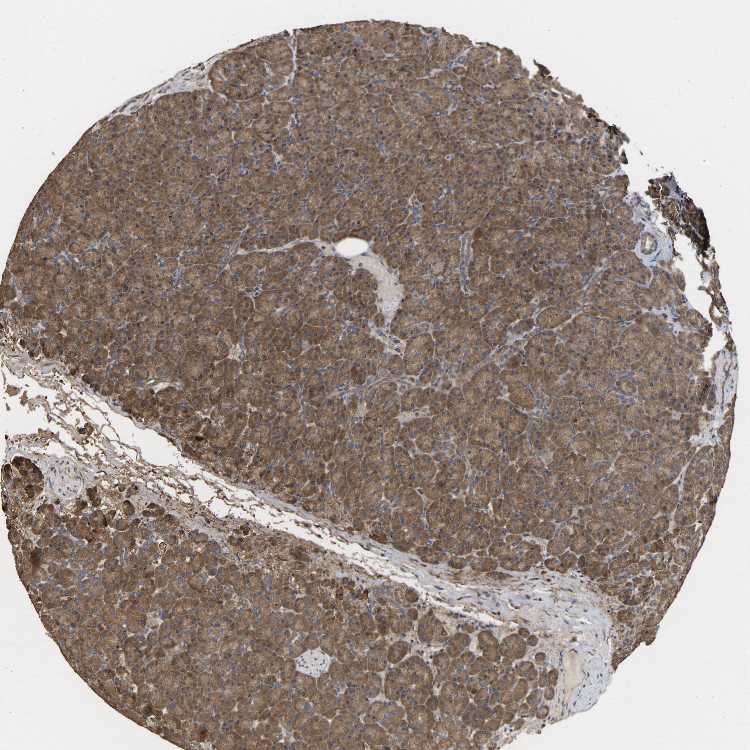

PANCREAS - Antibody stainingi

Antibody staining in the annotated cell types in the current human tissue is reported as not detected, low, medium, or high, based on conventional immunohistochemistry profiling in selected tissues. This score is based on the combination of the staining intensity and fraction of stained cells.

Each image is clickable and will lead to virtual microscopy that enables deeper exploration of all samples and also displays staining intensity scores, fraction scores and subcellular localization as well as patient and tissue information for each sample.

Antibody HPA019098Antibody HPA020057

Exocrine glandular cells MediumMedium

Pancreatic endocrine cells MediumLow